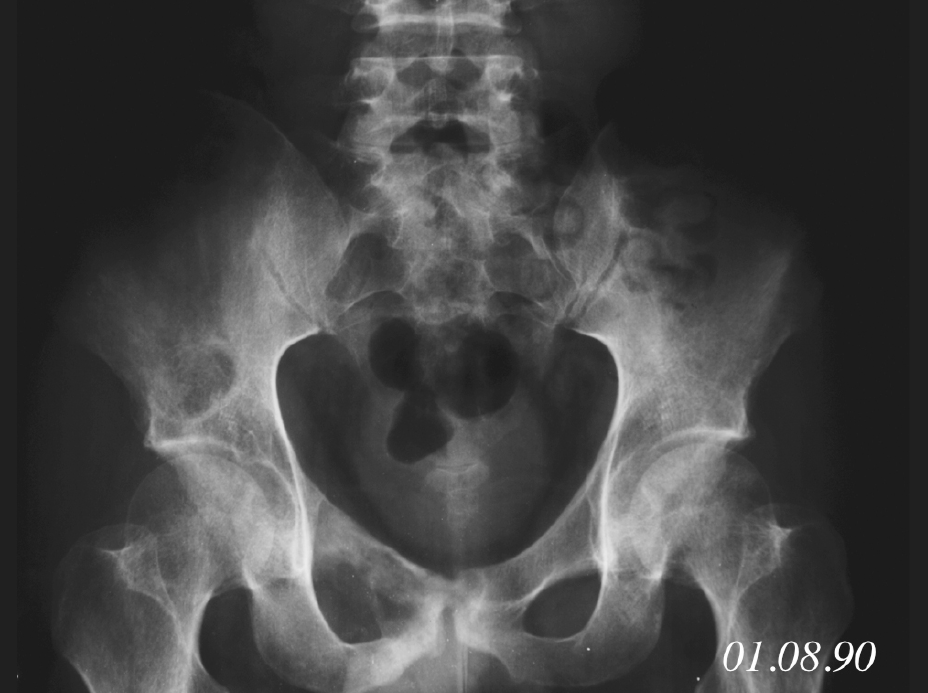

Figure4